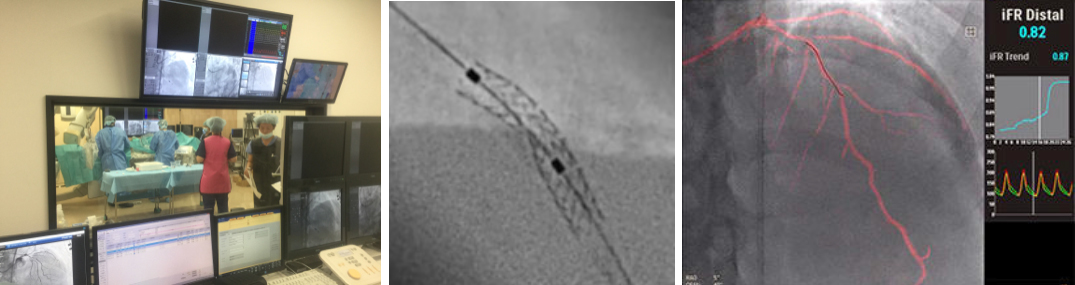

サブトラクション冠動脈CT

通常の画像(左)ではSTENT内の評価は困難ですが、サブトラクション画像(中央)によって末梢側に高度狭窄を疑われます(矢印)。カテーテル造影(右)でも同様の位置に高度狭窄病変を認めます(矢印)。

Yamaguchi T. Ichikawa K, Takahashi D. et.al. A New Contrast Enhancement Protocol for Subtraction Coronary Computed Tomography Requiring a Short Breath-Holding Time. Academic Radiology Published online: October 17, 2016